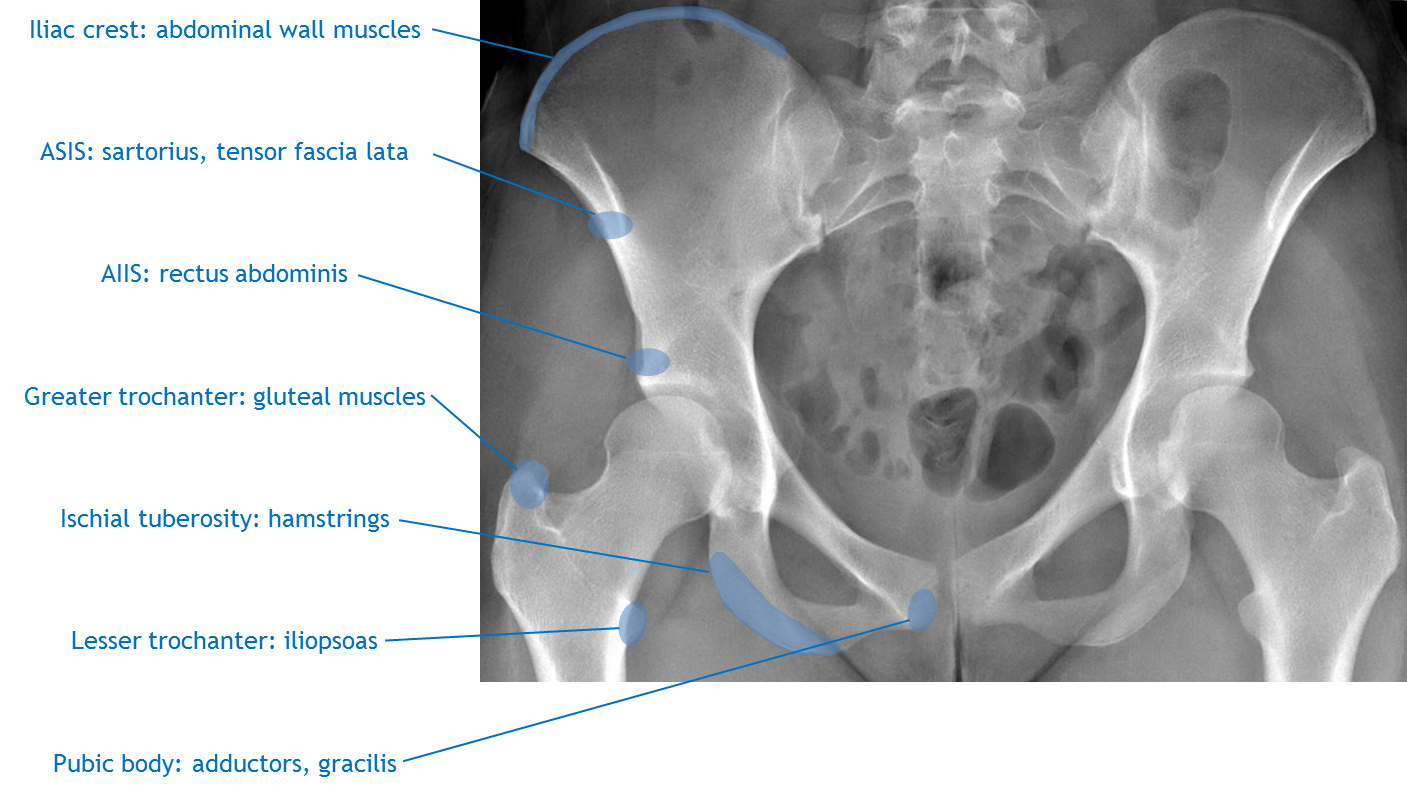

Attachments include the inguinal ligament, sartorius. Head neck greater trochanter intertrochanteric line lesser trochanter. Carry it anteriorly to the anterior superior iliac spine and distally and slightly laterally 10 to 12 cm. Cranial to the acetabulum, the ilium also has. The anterior superior iliac spine (abbreviated:

Cranial to the acetabulum, the ilium also has. Anterior superior iliac spine is a bony projection represents the anterior edge of iliac crest, which connects with the lateral point of the inguinal ligament.the subcutaneous anterior superior. Sacrum, iliac crest, spinous process and transverse process (lumbar) superior attachment: It refers to the anterior extremity of the iliac crest of the pelvis, which provides attachment for the inguinal ligament, and the sartorius muscle. With the close relations of the subcostal nerve to the anterior superior iliac spine, it can be at risk from damage during autologous bone harvesting from. Bone attachment of the upper limb with the axial skeleton. Anterior to posterior talus (ankle) mobilization. The anterior superior iliac spine is an important bony surface landmark and is the prominence is the most anterior part of the ilium.

Asis) is a bony projection of the iliac bone and an important landmark of surface anatomy. The anterior superior iliac spine (abbreviated: The scapula is a large, flat triangular bone that is suspended on the posterior wall of the ribcage by its muscular everters work together to stabilize the foot. It refers to the anterior extremity of the iliac crest of the pelvis, which provides attachment for the inguinal ligament, and the sartorius muscle. The anterior superior iliac spine is the uppermost of projection on anterior border of the ala of ilium, situated at the junction of the crest and anterior border; The anterior superior iliac spine (abbreviated: Lumbar spine palpation | clinical physio. Divide the superficial and deep fasciae. Transversus abominis has an anterior attachment on the iliac crest, an ideal place to act on the ilium producing compression of the sij in positioning the pelvic belt just below the anterior superior iliac spines (the high position) is more effective than the low position (at the top of the pubic symphysis). Subscribe to learn interesting facts about the human body every day. With the close relations of the subcostal nerve to the anterior superior iliac spine, it can be at risk from damage during autologous bone harvesting from. It provides attachment for the inguinal ligament, and the sartorius muscle. The anterior superior iliac spine (abbreviated:

Anterior superior iliac spine (asis). Superiorly is the anterior superior iliac spine (asis), and inferiorly is the anterior. The anterior superior iliac spine is the uppermost of projection on anterior border of the ala of ilium, situated at the junction of the crest and anterior border; Its outer border gives attachment to the fascia lata, and the tensor fasciæ latæ, its inner border, to the iliacus; The scapula is a large, flat triangular bone that is suspended on the posterior wall of the ribcage by its muscular everters work together to stabilize the foot.

Its outer border gives attachment to the fascia lata, and the tensor fasciæ latæ, its inner border, to the iliacus; With the close relations of the subcostal nerve to the anterior superior iliac spine, it can be at risk from damage during autologous bone harvesting from. Strip the periosteum with the attachments of the gluteus medius and minimus muscles from the lateral surface of the ilium using a periosteal elevator. The anterior superior iliac spine is an important bony surface landmark and is the prominence is the most anterior part of the ilium. Sacrum, iliac crest, spinous process and transverse process (lumbar) superior attachment: Asis (sartorius attachment), anterior inferior iliac spine (aiis, rectus femoral attachment) and ischial tuberosity (hamstrings and adductor attachment). Carry it anteriorly to the anterior superior iliac spine and distally and slightly laterally 10 to 12 cm. The child is encouraged to lie on the table in a supine position.

Cranial to the acetabulum, the ilium also has. Sacrum, iliac crest, spinous process and transverse process (lumbar) superior attachment: The anterior superior iliac spine (abbreviated: Bone attachment of the upper limb with the axial skeleton. Superior gluteal artery (dorsal view). Three assessments of the symmetry of the anterior superior iliac spine (asis), posterior superior iliac spine (psis), medial malleoli (mm), sacral inferior lateral angle (sila) and sft were performed on every subject by all examiners. Carry it anteriorly to the anterior superior iliac spine and distally and slightly laterally 10 to 12 cm. There are projections in this bone that serve as 1 anterior superior iliac spine clinical anatomy. Anterior superior iliac spine (asis) to the medial proximal anterior tibia just below the condyle (as one of the pes anserinus muscles). With the close relations of the subcostal nerve to the anterior superior iliac spine, it can be at risk from damage during autologous bone harvesting from. The abscess is an infected space there. Hip to include the anterior superior iliac spine superiorly, the symphysis pubis to the lateral wall of the the hip bones give rise to many muscular attachments. Asis) is a bony projection of the iliac bone and an important landmark of surface anatomy.

Asis (sartorius attachment), anterior inferior iliac spine (aiis, rectus femoral attachment) and ischial tuberosity (hamstrings and adductor attachment). The anterior superior iliac spine is an important bony surface landmark and is the prominence is the most anterior part of the ilium. Anterior to posterior talus (ankle) mobilization. Asis) is a bony projection of the iliac bone and an important landmark of surface anatomy. The anterior part of the ilium consists of two bony spines. It refers to the anterior extremity of the iliac crest of the pelvis. Iliac fossa (fossa iliaca) is a broad depression located along the anteromedial surface, inferior to the iliac crest. There are two muscles that produce inversion, tibialis anterior, and tibialis posterior.